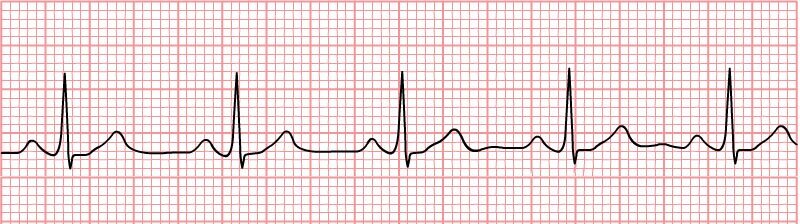

- elektrokardiografia (EKG) – pozwala wykryć zaburzenia rytmu i niedokrwienie serca,